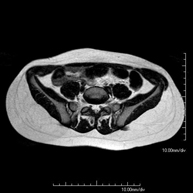

- Sacroiliac MRI

Study specifically designed to assess these joints and their inflammation in patients suffering from ankylosing spondylitis. It is also useful in patients with trauma and possible fractures of the sacrum and coccyx. It lasts approximately 16 minutes. It is a radiation-free procedure.